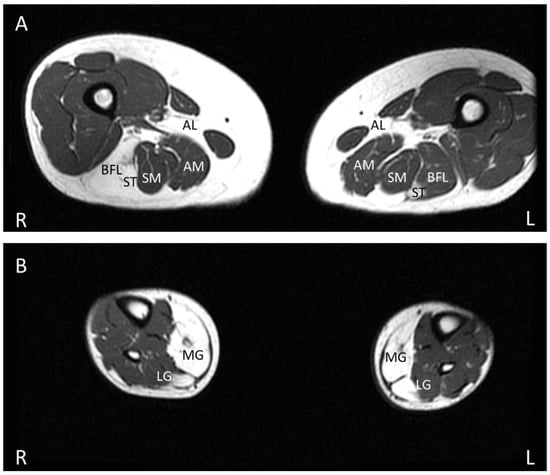

8. Muscle MRI

- Khawajazada, T.; Kass, K.; Rudolf, K.; de Stricker Borch, J.; Sheikh, A.M.; Witting, N.; Vissing, J. Muscle involvement assessed by quantitative magnetic resonance imaging in patients with anoctamin 5 deficiency. Eur. J. Neurol. 2021, 28, 3121–3132. [Google Scholar] [CrossRef] [PubMed]

- Mahjneh, I.; Bashir, R.; Kiuru-Enari, S.; Linssen, W.; Lamminen, A.; Visser, M. Selective pattern of muscle involvement seen in distal muscular dystrophy associated with anoctamin 5 mutations: A follow-up muscle MRI study. Neuromuscul. Disord. NMD 2012, 22 (Suppl. S2), S130–S136. [Google Scholar] [CrossRef]

- Sarkozy, A.; Deschauer, M.; Carlier, R.Y.; Schrank, B.; Seeger, J.; Walter, M.C.; Schoser, B.; Reilich, P.; Leturq, F.; Radunovic, A.; et al. Muscle MRI findings in limb girdle muscular dystrophy type 2L. Neuromuscul. Disord. NMD 2012, 22 (Suppl. S2), S122–S129. [Google Scholar] [CrossRef] [PubMed]

- Holm-Yildiz, S.; Witting, N.; de Stricker Borch, J.; Kass, K.; Khawajazada, T.; Krag, T.; Vissing, J. Muscle biopsy and MRI findings in ANO5-related myopathy. Muscle Nerve 2021, 64, 743–748. [Google Scholar] [CrossRef] [PubMed]

- De Wel, B.; Huysmans, L.; Peeters, R.; Goosens, V.; Ghysels, S.; Byloos, K.; Putzeys, G.; D’Hondt, A.; De Bleecker, J.L.; Dupont, P.; et al. Prospective Natural History Study in 24 Adult Patients With LGMDR12 Over 2 Years’ Follow-up: Quantitative MRI and Clinical Outcome Measures. Neurology 2022, 99, e638–e649. [Google Scholar] [CrossRef]

- Leung, D.G. Magnetic resonance imaging patterns of muscle involvement in genetic muscle diseases: A systematic review. J. Neurol. 2017, 264, 1320–1333. [Google Scholar] [CrossRef]

- Diaz-Manera, J.; Fernandez-Torron, R.; Llauger, J.; James, M.K.; Mayhew, A.; Smith, F.E.; Moore, U.R.; Blamire, A.M.; Carlier, P.G.; Rufibach, L.; et al. Muscle MRI in patients with dysferlinopathy: Pattern recognition and implications for clinical trials. J. Neurol. Neurosurg. Psychiatry 2018, 89, 1071. [Google Scholar] [CrossRef]